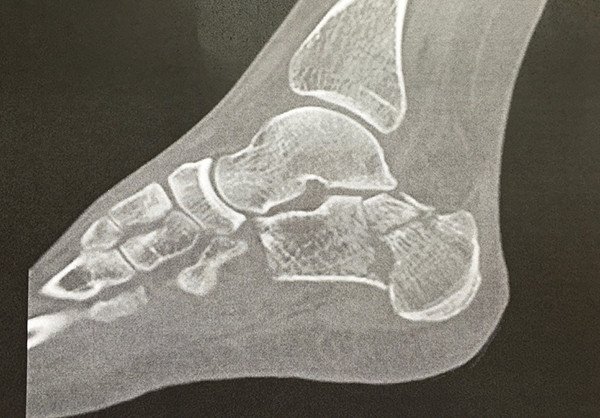

Da auf den Aufnahmen der Computertomografie (Abb. 4) bereits eine – durch die Fraktur bedingte – schwere Arthrose zwischen Sprung- und Fersenbein, welche gemeinsam das untere Sprunggelenk bilden, nachweisbar war, sahen wir eine alleinige Entfernung des Osteosynthesematerials als nicht erfolgsversprechend an und empfahlen der Patientin zusätzlich eine Versteifung dieses Gelenkes. Hierbei kommt es lediglich zu einer geringen Funktionseinbusse des Fusses und ist die einzige sinnvolle Option bei einer posttraumatischen Arthrose in diesem Bereich.